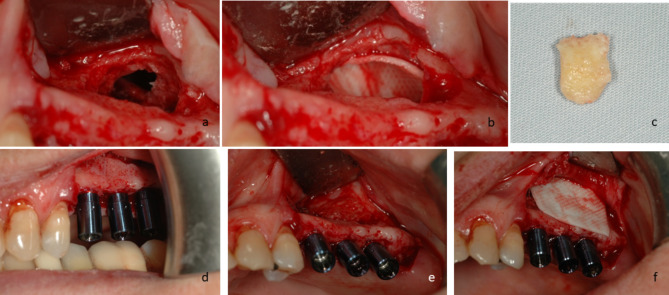

Objectives: Perforation of the Schneiderian membrane (SM) is a common intraoperative complication of sinus augmentation. This study aimed to evaluate risk factors for SM perforation, and to compare clinical outcomes between patients with SM perforation repaired using crosslinked collagen membranes (CLM) compared to those with an intact SM.

Methods: A retrospective cohort study was conducted at a single tertiary medical center. Data was collected on patients requiring sinus augmentation via lateral approach prior to implant placement. The collected data included demographics, surgical details, implant outcomes, radiographic analysis, and presence of SM perforation. In cases of perforation a CLM was used to repair the SM. Statistical analysis was performed to evaluate risk factors for perforation and whether SM perforation repair using CLM influenced early implant failure (EIF). A p-value < 0.05 was considered significant.

Results: Data on 194 individuals who underwent 278 lateral approach sinus augmentation procedures was collected. SM perforation occurred in 66 (23.74%) sinuses. Treatment of SM perforation using CLM yielded similar results to sinuses without perforations: EIF and the augmented gained bone did not correlate with SM perforation. Younger patients, and thick SMs (> 3 mm) had significantly lower risk of perforation.

Conclusions: Older age and thinner SMs are risk factors for sinus membrane perforations. No significant differences in bone gain and EIF were found between perforated and intact membranes.

Clinical relevance: Schneiderian membrane perforation repair using crosslinked collagen membrane provides comparable results to sinus augmentations without perforations, demonstrating its effectiveness in preventing complications.